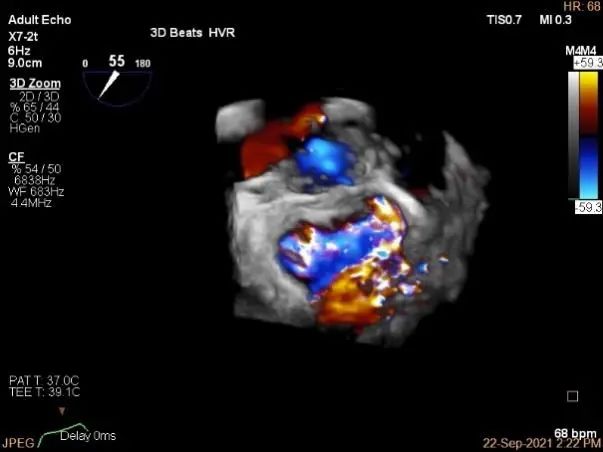

术中超声

3D-color,返流重度,3+级

三维评估两个夹子位置

3D-color再次确定未见残余分流